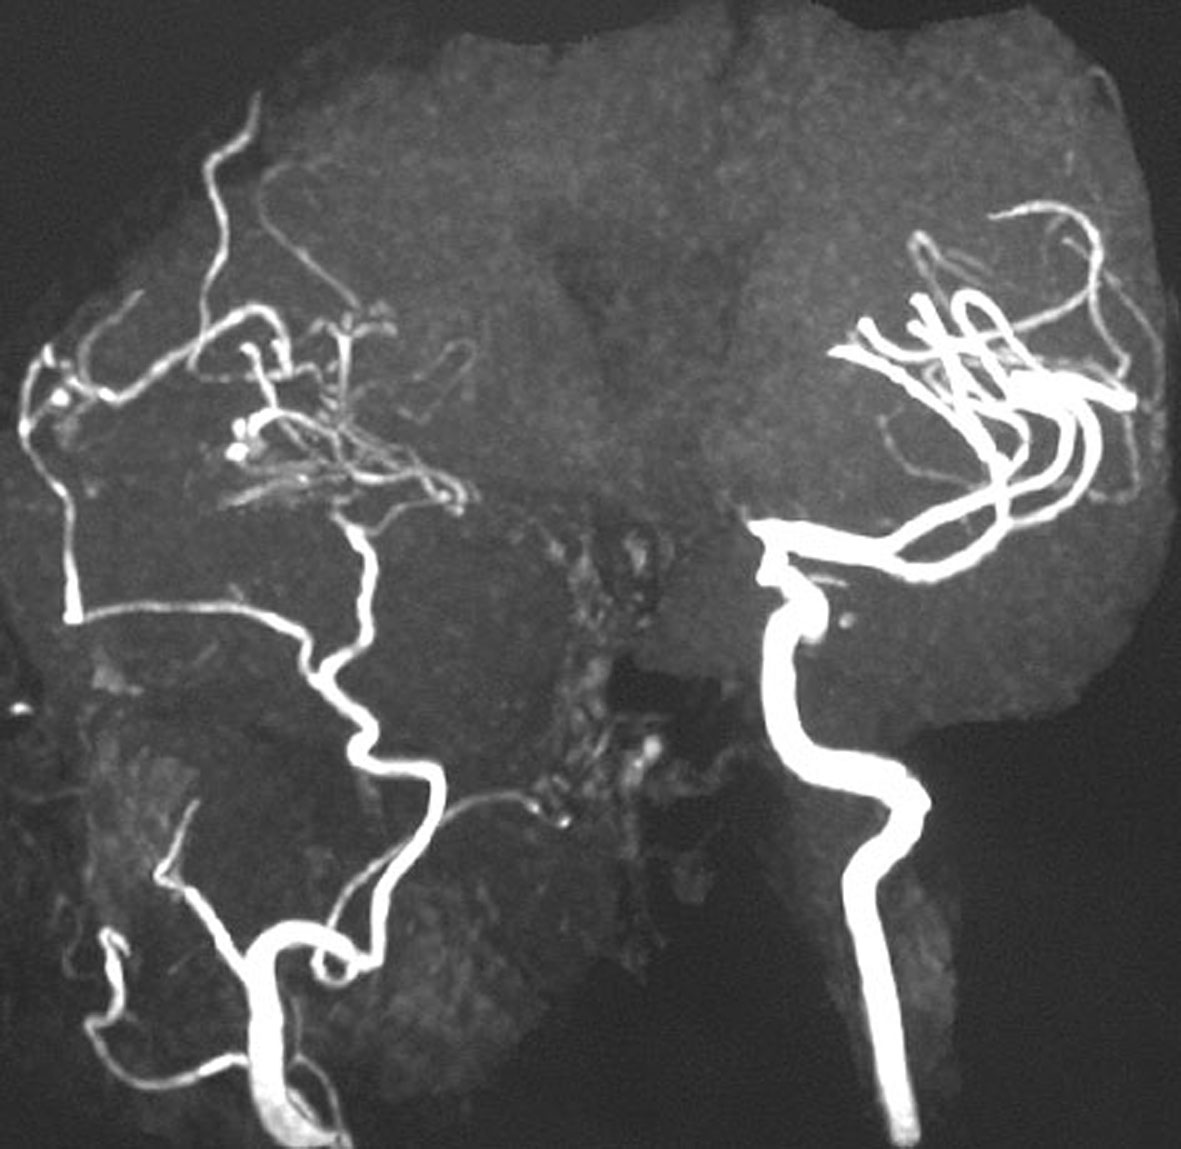

4歳の時に頭蓋咽頭腫に対して50グレイの分割照射を受けました。両側の内頸動脈と前交通動脈が被曝しています。16歳(12年後)に左片麻痺の虚血発作を生じました。右内頸動脈が閉塞してウィルス動脈輪閉塞(モヤモヤ病)になっていました。前交通動脈に動脈瘤(赤矢印)もできていました。小児の頭蓋咽頭腫への放射線治療ではかなり高率に閉塞性脳血管障害を生じるのですが,治療後10年以上がたってから起るので,治療を行った医師はそれをみることはほとんどありません。

小児のクラニオ:放射線治療後の脳梗塞

3歳の時に鞍上部クラニオに40グレイの放射線治療を受けました。31歳(28年後)で右前頭葉に脳梗塞を生じました。右内頸動脈と左前大脳動脈が閉塞したウィルス動脈輪閉塞症(モヤモヤ病)になっています。右の中硬膜動脈から右大脳に血流が入っています。

5歳でガンマナイフ,8歳と10歳の時にサイバーナイフ治療を受けました。右内頸動脈が閉塞してウィルス動脈輪閉塞(モヤモヤ病)になりました。この画像は10歳時のものです。右中硬膜動脈から右の前頭葉と側頭葉に血流が入っていてモヤモヤ病の病態です。脳虚血発作や脳梗塞はない無症候性のものです。